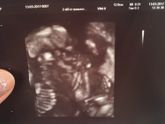

13 марта 2017 14:13

Пошла на узи потому что пропали отчетливые частые шевелюхи, и вообще что то переживать стала по некоторым причинам.. Но все хорошо) Врач умилялась вместе со мной, сын глотал воды и выплевывал, и аж две руки пытался в рот засунуть, так вкусно было … Читать далее